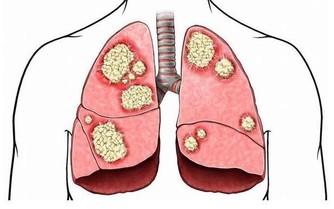

腎病被稱為〝沉默殺手〞,就算腎受傷了,你可能也毫無感覺。

你經常在新聞中看到,某人因食慾減退、貧血或疲勞乏力去就醫,卻發現已經是尿毒癥晚期!

實際上,中國每10人中即有1人患有腎臟疾病!

據最新發表在國際頂尖醫學雜誌《柳葉刀》上的一項研究報導,中國成人慢性腎臟病患病率高達10.8%。